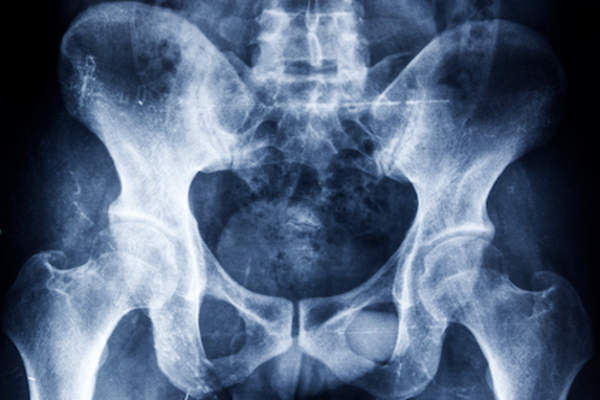

骨质疏松症是一种骨骼变薄变弱,增加骨折风险的疾病。一个普遍的误解是,骨质疏松症是一种“老年人的疾病”。But while most women don't see the effects until later in life, factors earlier in your life will directly contribute to your potential to develop this condition later. While some risk factors for osteoporosis can’t be changed, there are certain steps you can take to help降低风险。请仔细阅读,了解他们。

遗传因素可以通过30岁贡献高达峰值骨量的75%,根据美国国立卫生研究院(NIH)。最引人注目的因素是骨质疏松症或骨折家族史(尤其是在母系)。不幸的是,这是你失控的危险因素。性别,种族和种族都遗传风险因素。

虽然男人可以得到骨质疏松症,约80%的与条件的美国人是女性,根据国家骨质疏松基金会(NOF)。此外,为50岁以上的大大增加你的风险。此外,谁在以后的年龄有他们的第一期的妇女可能也增加了风险。同样,更年期导致骨质流失,所以如果你已经达到生命的阶段,你有一个发展这种情况的机会较大。

当涉及到种族和族裔,白人妇女患骨质疏松症的风险最高,根据美国国立卫生研究院。这种增加的风险可能是骨质密度差异的结果。例如,非洲裔妇女往往有较高的峰值骨量。